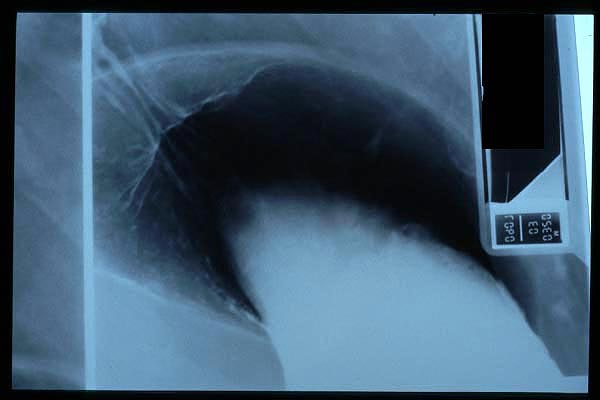

Fractura impactada de húmero .